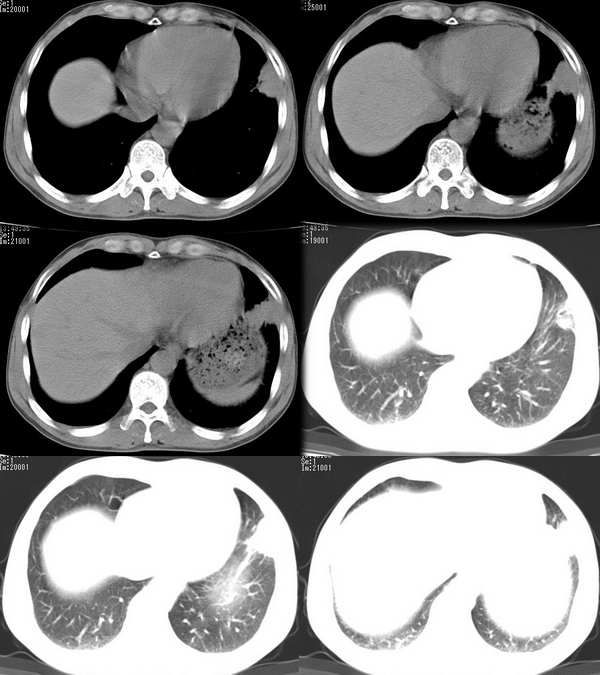

再来个空洞性肺癌,男,58岁,有咳嗽,咳痰,咯血,我看到片子时已经是治疗后复查了,第一次片子,空洞里充满了积液。